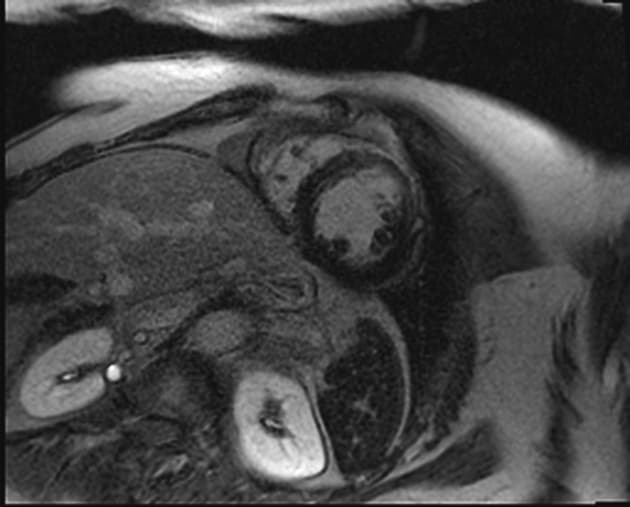

- Bệnh cơ tim phì đại dạng đỉnh thất (apical hypertrophic cardiomyopathy) với tắc nghẽn ở đoạn giữa thất (midventricular obstruction).

- Cả chuỗi hình ảnh LGE và PSIR có tiêm thuốc đối quang (gadolinium) đều cho thấy xơ hóa thành thất dạng ổ (patchy midwall fibrosis), có liên quan đến lớp dưới nội tâm mạc (subendocardial involvement) tại đỉnh thất (apex).

- Necrosis dưới nội tâm mạc ở đỉnh thất (apical subendocardial necrosis) có thể là nguyên nhân gây đau ngực (chest pain).

- Không thấy huyết khối (no thrombus).

- "Tắc nghẽn đoạn giữa thất có thể gây tăng áp lực trong buồng tim và thiếu máu cơ tim vùng đỉnh, dẫn đến hoại tử và xơ hóa lớp dưới nội tâm mạc."

- "Hình ảnh tăng sáng muộn (LGE) ở vùng dưới nội tâm mạc đỉnh giúp phân biệt tình trạng này với các nguyên nhân khác gây dày thành tim vùng đỉnh."

Bệnh cơ tim phì đại dạng đỉnh thất là một thể hình thái riêng biệt của bệnh cơ tim phì đại do bất thường sợi co cơ, chủ yếu ảnh hưởng đến đỉnh thất trái. Khác với thể phì đại vách không đối xứng phổ biến hơn, thể này biểu hiện bằng sự dày lên cô lập ở vùng đỉnh, thường dẫn đến tắc nghẽn đoạn giữa thất và tạo gradient áp lực. Tình trạng căng thẳng huyết động này có thể gây thiếu máu cơ tim vùng đỉnh, hoại tử lớp dưới nội tâm mạc và xơ hóa thành thất dạng ổ, như thấy trên hình ảnh cộng hưởng từ tăng sáng muộn. Sự hiện diện của mô xơ liên quan đến nguy cơ cao hơn về rối loạn nhịp và các biến cố tim bất lợi, làm tiên lượng có thể xấu hơn. Chẩn đoán phân biệt bao gồm nhồi máu cơ tim, bệnh cơ tim do amyloid và sarcoid, nhưng hình ảnh đặc trưng dạng 'bích' trên chụp buồng thất trái và sự vắng mặt của bệnh động mạch vành giúp khẳng định chẩn đoán.